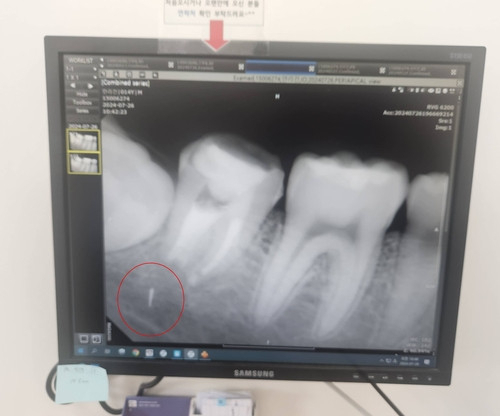

그러나 치료 후에도 통증과 염증이 계속됐고, 한 달여 후 엑스레이 촬영을 통해 충격적인 사실을 확인했다. 치료 과정에서 부러진 의료기기 조각이 치아 뿌리에 남아 있었던 것이다. 안군의 성장에 따라 조각은 치아 뿌리에서 턱으로 서서히 이동하기까지 했다.

상급병원으로 옮긴 안군은 그해 가을 치아를 뽑고 턱뼈를 갈아내 조각을 제거한 뒤 다시 치아를 심는 수술대에 올랐다. 하지만 의료진은 수술 중 조각이 턱 신경과 너무 가까이 있어 무리하게 제거할 경우 신경 손상 위험이 크다고 판단했다. 결국 조각은 제거되지 못한 채 지금도 안군의 턱뼈 안에 박혀 있다.